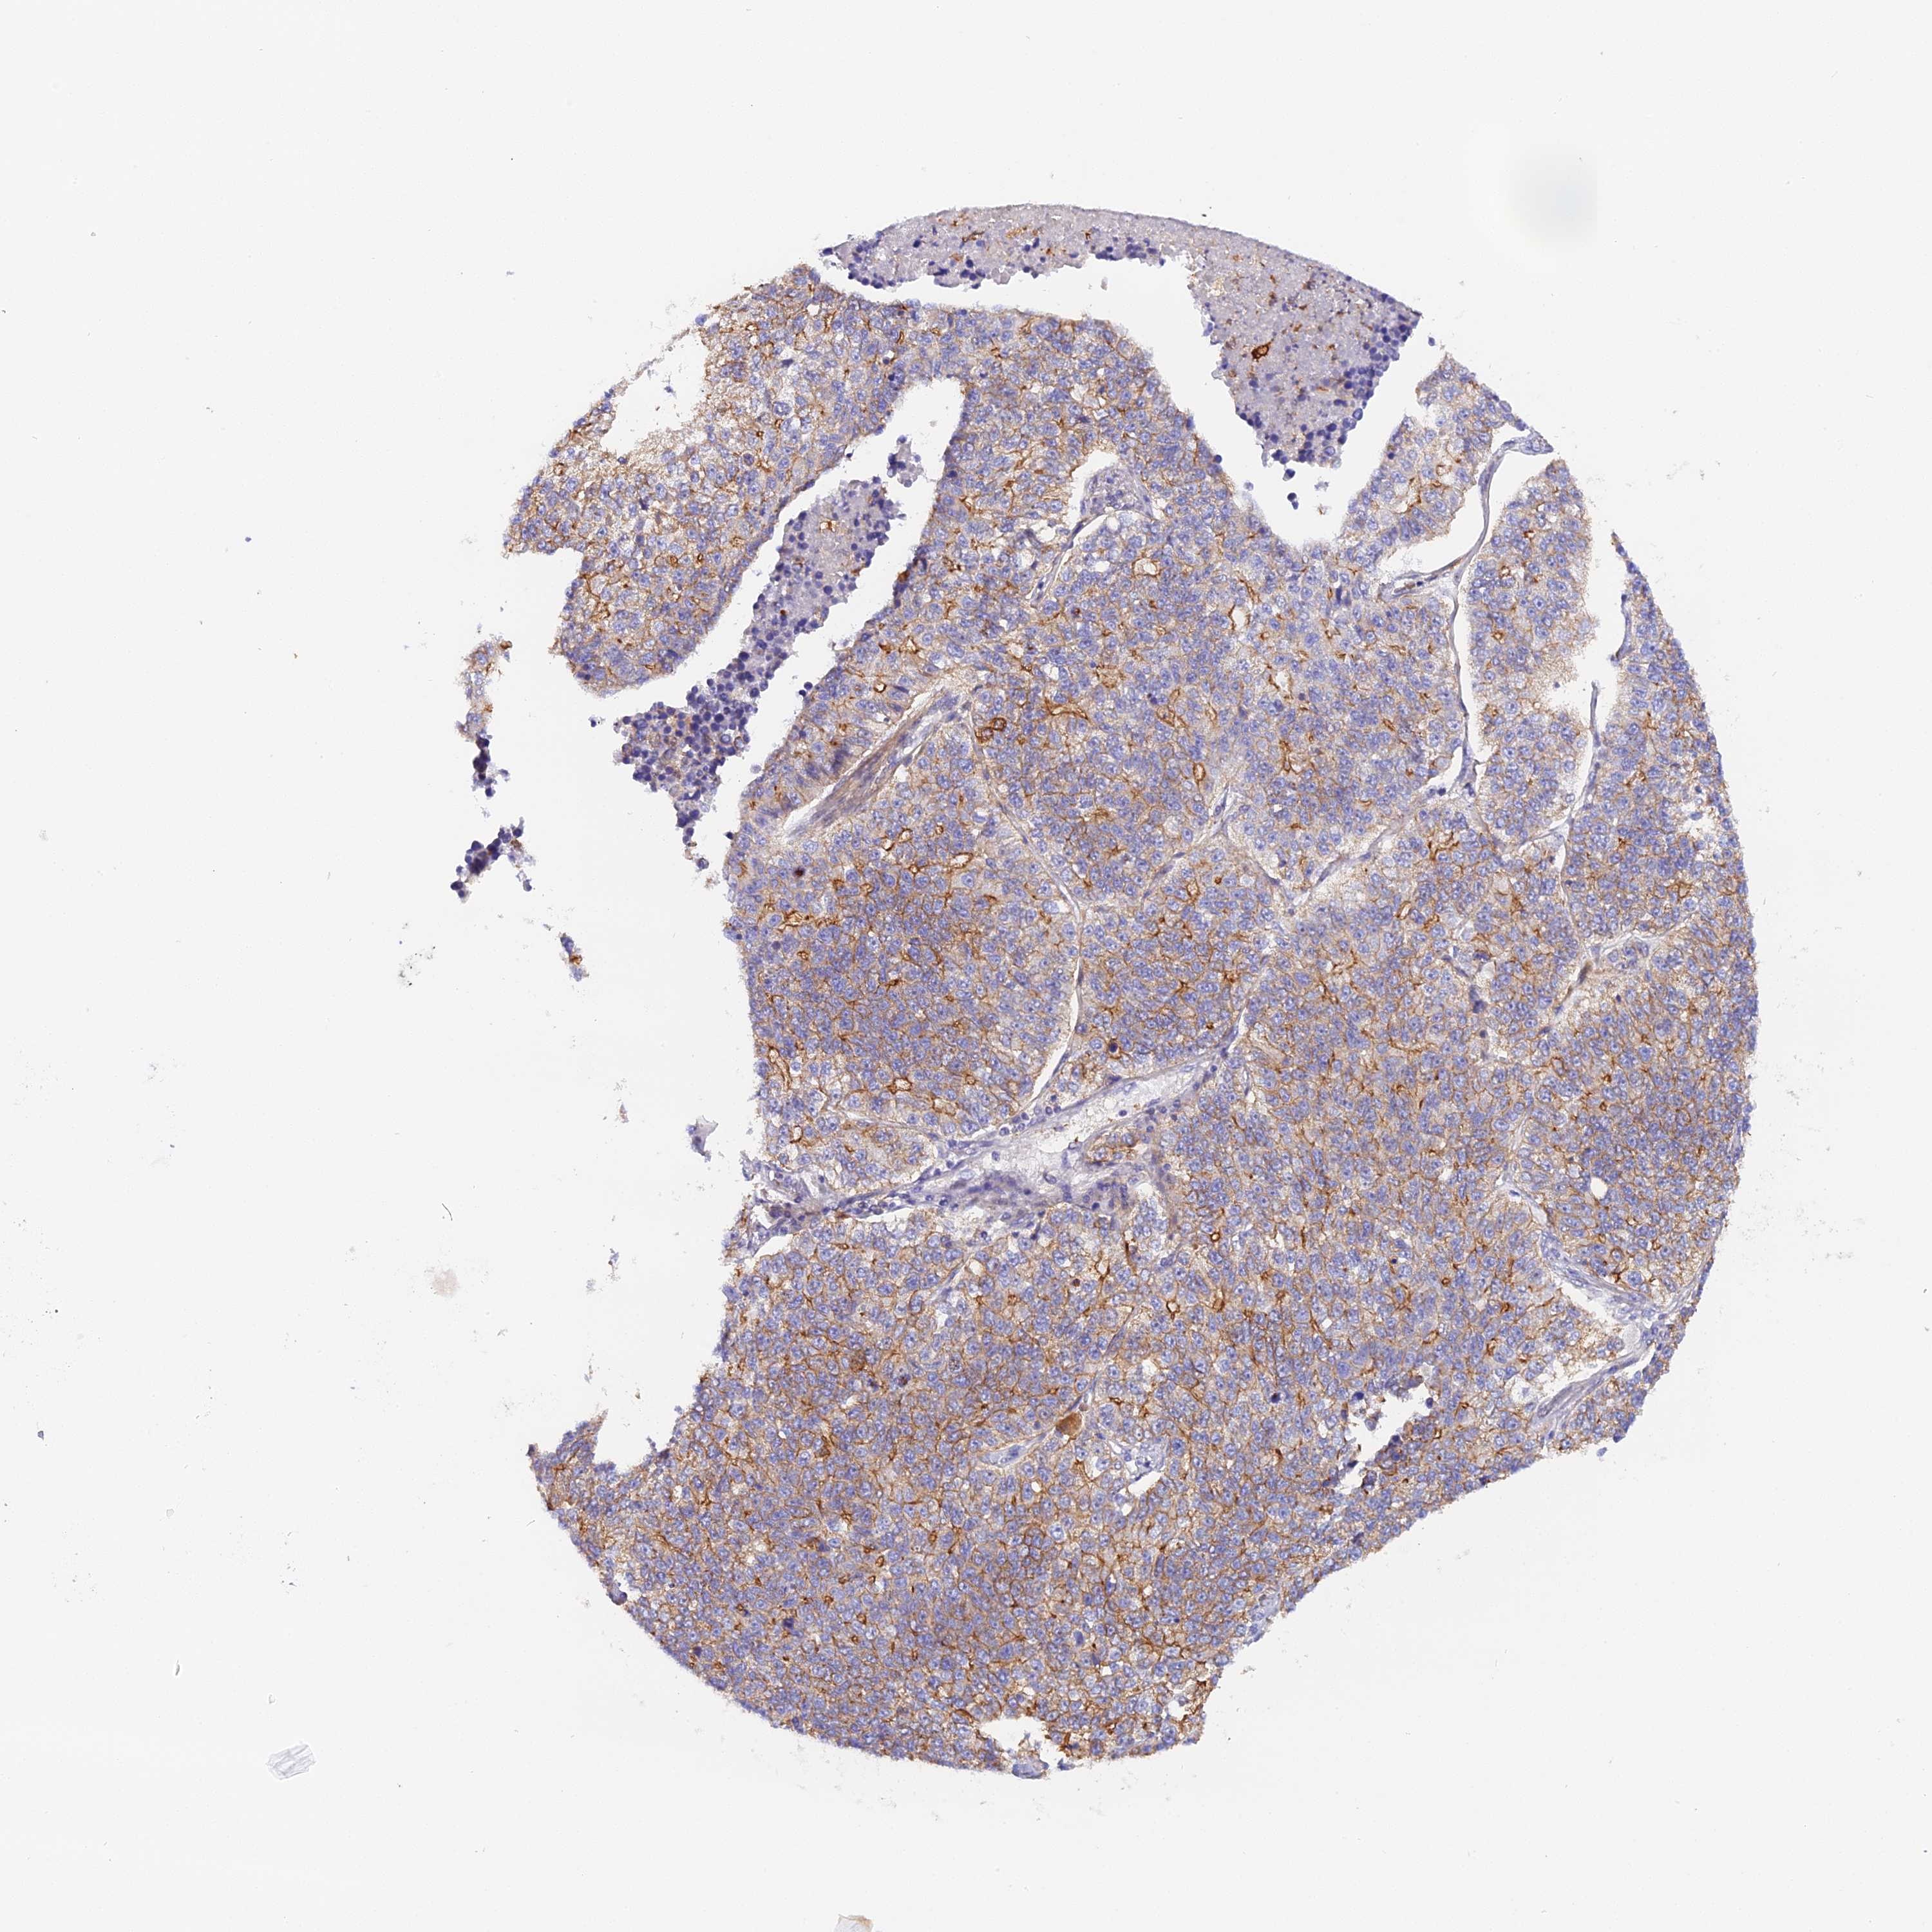

LUNG ADENOCARCINOMA (TCGA) - Interactive survival scatter ploti

The Survival Scatter plot shows the clinical status (i.e. dead or alive) for all individuals in the patient cohort, based on the same data that underlies the corresponding Kaplan-Meier plots. Patients that are alive at last time for follow-up are shown in blue and patients who have died during the study are shown in red.

The x-axis shows the expression levels (FPKM) of the investigated gene in the tumor tissue at the time of diagnosis. The y-axis shows the follow-up time after diagnosis (years). Both axes are complimented with kernel density curves demonstrating the data density over the axes. The top density plot shows the expression levels (FPKM) distribution among dead (red) and alive patients (blue). The right density plot shows the data density of the survived years of dead patients with high and low expression levels respectively, stratified using the cutoff indicated by the vertical dashed line through the Survival Scatter plot. This cutoff is automatically defined based on the FPKM cutoff that minimizes the p-score. The cutoff can be changed by dragging the vertical line or by entering a cutoff value in the square labeled "Current cut-off".

Under the Survival Scatter plot the p-score landscape (black curve; left axis) is shown together with dead median separation (red curve; right axis). Dead median separation is the difference in median mRNA expression between patients who have died with high and low expression, respectively. It is calculated as follows: median FPKM expression of dead patients with high expression - median FPKM expression of dead patients with low expression. This is intended to aid the user in visually exploring custom cutoffs and the associated p-scores and dead median separation.

Individual patient data is displayed and can be filtered by clicking on one or more of the category buttons on the top of the page. Categories describing expression level and patient information include: high, low, alive, dead, female, male and tumor stages. The scale of the x-axis can be toggled between linear and log-scale by clicking on the "x log" button. Mouse-over function shows TCGA ID, patient information and mRNA expression (FPKM) for each patient.

& Survival analysisi

Kaplan-Meier plots summarize results from analysis of correlation between mRNA expression level and patient survival. Patients were divided based on level of expression into one of the two groups "low" (under cut off) or "high" (over cut off). X-axis shows time for survival (years) and y-axis shows the probability of survival, where 1.0 corresponds to 100 percent.

KATNB1 is not prognostic in Lung Adenocarcinoma (TCGA)

: 18.88